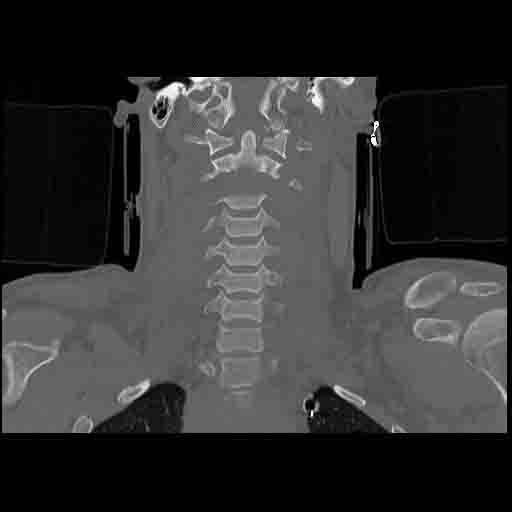

NEWCASTLE – Tony Cowan, 29 anni, è riuscito a sopravvivere, contro ogni pronostico medico, dopo che la testa è stata recisa dalla colonna vertebrale in un brutto incidente.

I tessuti muscolari hanno evitato che si staccasse dal collo dopo che la sua auto subì un brusco impatto dopo averne perso il controllo. Secondo quanto riporta Metro.co.uk, Tony, un ex muratore è riuscito a sopravvivere ma oggi è costretto a stare su una sedia a rotelle e a comunicare attraverso una macchina.